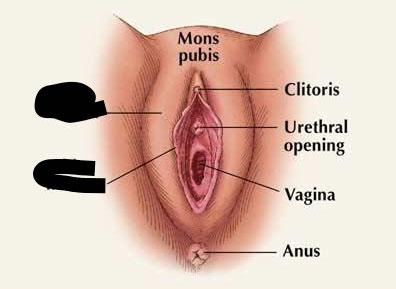

Clitoris

External urethral orifice (female)

Labia majora/minora

Prepuce (=clitoral hood)

Vagina

Vaginal orifice

Vestibule (of vulva)

Anus